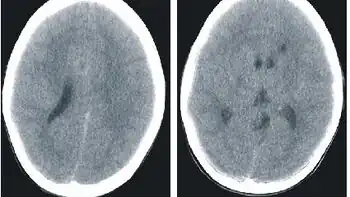

.jpg)

Histidenemia is characterized by increased levels of histidine, histamine and imidazole in blood, urine and cerebrospinal fluid. This also results in decreased levels of the metabolite urocanic acid in blood, urine, and skin cells.[1]

In Japan, neonatal screening was previously performed on infants within one month of birth; infants demonstrating a blood histidine level of 6 mg/dl or more underwent careful testing as suspected histidinemia cases.[6]

A typical characteristic of histidinemia is an increase in the blood histidine levels from normal levels (70–120 μM) to an elevated level (290–1420 μM).[3] Further testing includes: observing histidine as well as imidazolepyruvic acid metabolites in the urine. However, neonatal urine testing has been discontinued in most places, with the exception of Quebec.[3]